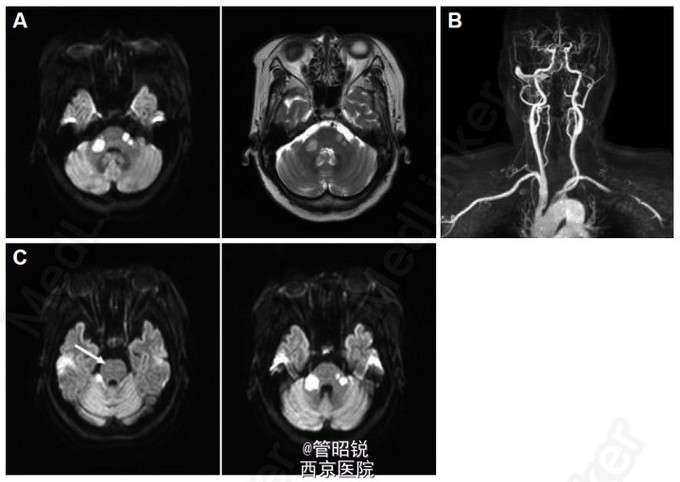

患者,女,71岁。有高血压和非胰岛素依赖型糖尿病病史。以突发的眩晕和共济失调入院。入院时血压146/98mmHg,心率97次/分,节律整齐。神经系统查体,神志清,除构音障碍外,无明显异常。小脑功能测试显示严重的共济失调,站立时需要扶持。双侧肱二头肌和膝反射减弱。巴彬斯基征阳性。T2WI 弥散加权显示双侧脑桥和右侧小脑急性腔梗。MRA显示严重的双侧椎动脉闭塞。给予口服阿司匹林治疗。三天后,病情进展为左眼外侧凝视受限和水平性复视。再次进行了检查,显示右侧脑桥正中旁的新发小的急性腔梗。静脉给予肝素治疗5天后,症状逐渐改善,但共济失调仍存在。转入康复医院1年后,眩晕减轻,可以扶拐行走。随访的T2WI显示橄榄脑桥小脑萎缩和脑桥十字征。